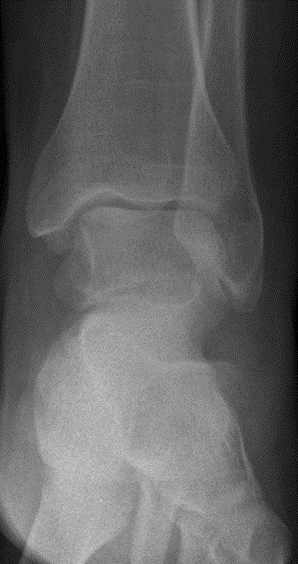

Die Röntgenuntersuchung ergab keinen pathologischen Befund. (Abb.1 und 2)

Abb.1 Unfallbild a.p.